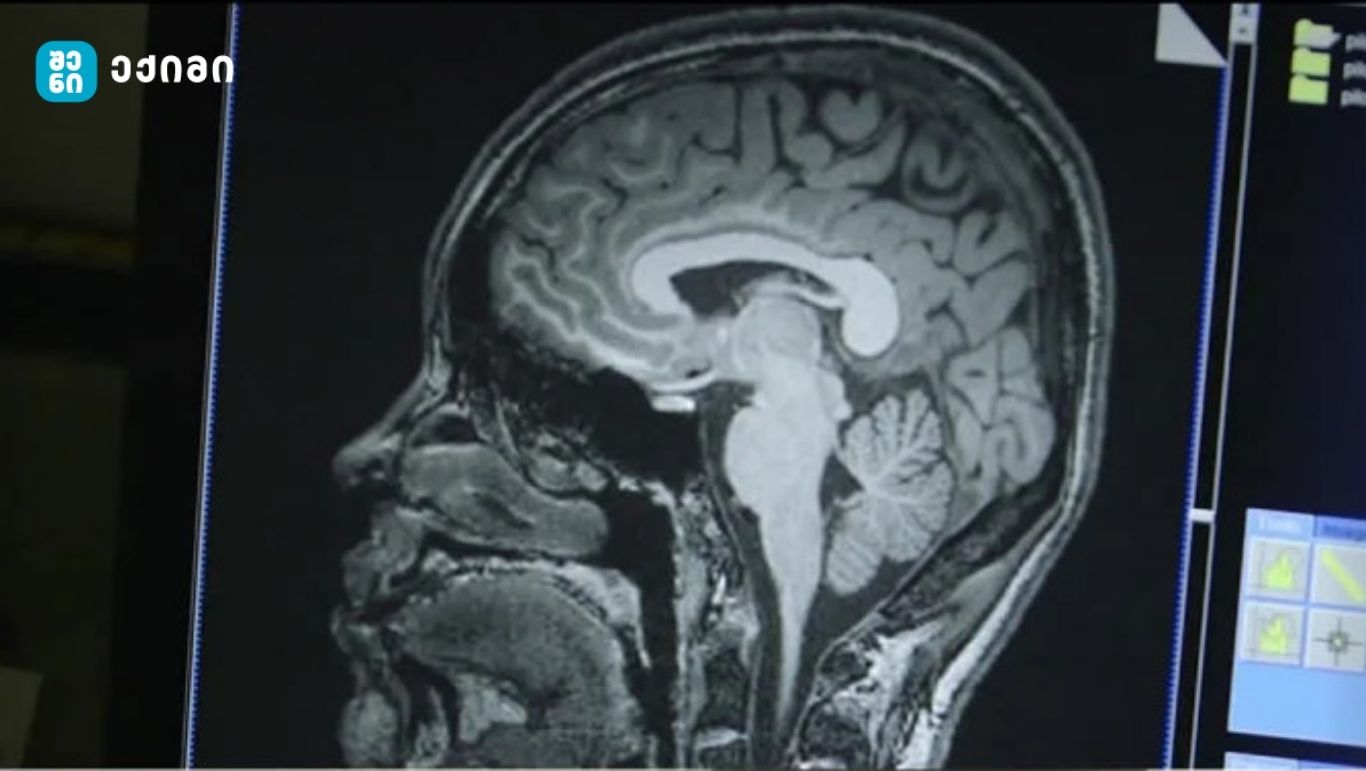

სიმსუქნე და ტვინი: ახალი კვლევები აჩვენებს პირდაპირ კავშირს ჭარბწონიანობასა და ნერვულ სისტემას შორის

თანამედროვე მეცნიერება სულ უფრო მეტ მტკიცებულებას აგროვებს იმის შესახებ, რომ სიმსუქნე არა მხოლოდ ფიზიკურ ჯანმრთელობაზე, არამედ ტვინის ფუნქციონირებასა და სტრუქტურაზეც ახდენს სერიოზულ ზემოქმედებას. ახალი კვლევების შედეგად დადგინდა, რომ ორგანიზმში ცხიმის გადაჭარბებული რაოდენობა პირდაპირ კავშირშია თავის ტვინის რუხი და თეთრი ნივთიერებების შემცირებასთან.

გაერთიანებული სამეფოს ბიობანკის მონაცემებზე დაყრდნობით ჩატარებულმა კვლევამ, რომელშიც 12,000-ზე მეტი ადამიანი მონაწილეობდა, გამოავლინა, რომ ცხიმის მაღალი დონე ტვინის სხვადასხვა უბნის სტრუქტურულ ცვლილებებს იწვევს. განსაკუთრებით აღსანიშნავია რუხი ნივთიერების შემცირება, რომელიც ნეირონებით მდიდარი ქერქოვანი სტრუქტურაა და პასუხისმგებელია ისეთ პროცესებზე, როგორებიცაა მეხსიერება, ყურადღება, ემოციები და გადაწყვეტილებების მიღება.